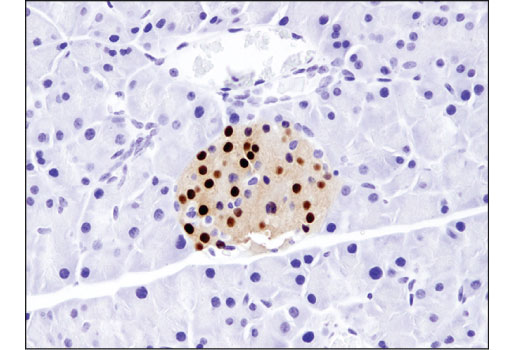

Immunohistochemical analysis of paraffin-embedded mouse pancreas using NKX6.1 (D8O4R) Rabbit mAb.

Immunohistochemistry Image 1: NKX6.1 (D8O4R) Rabbit Monoclonal Antibody